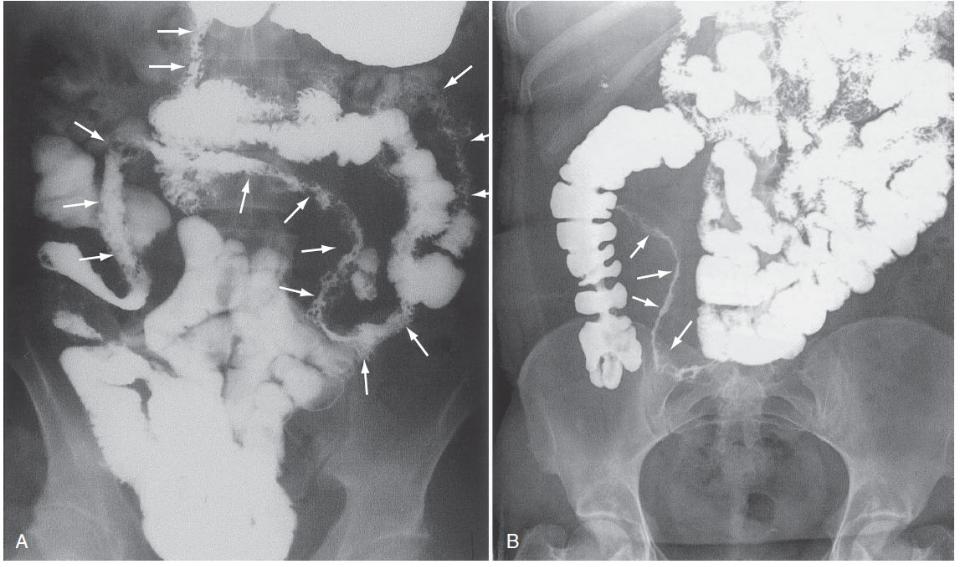

Болезнь Крона: рентгенологические признаки